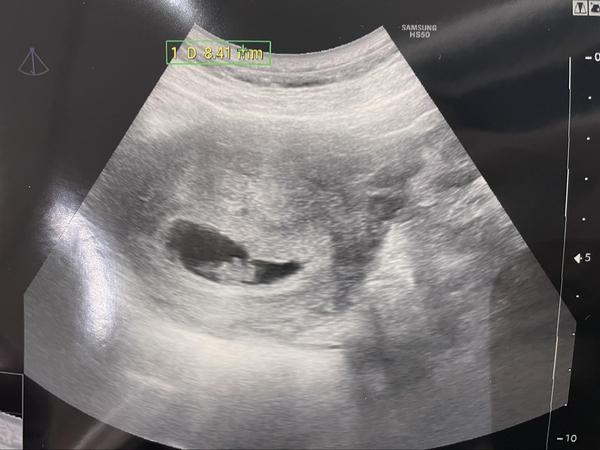

@hvezdicka09 mohu se zeptat jak to dopadlo? Vše v pořádku? Mám podobnou fotku 8+1 přes břicho 🙂

@hvezdicka09 mohu se zepta jak to dopadlo? Mám podobné foto ultrazvuku 8+1 přes břicho 🙂

@hvezdicka09 tak to je ta nejskvělejší zpráva !!! Já mám bych řekla trochu podobnou fotku, UZ je ale dělaný přes břicho, tak vlastně nic skoro nevidím oproti holkách co mají v tomto týdnu UZ spodem, tak jste mi udělala radost, že snad je vše na dobré cestě 🙂